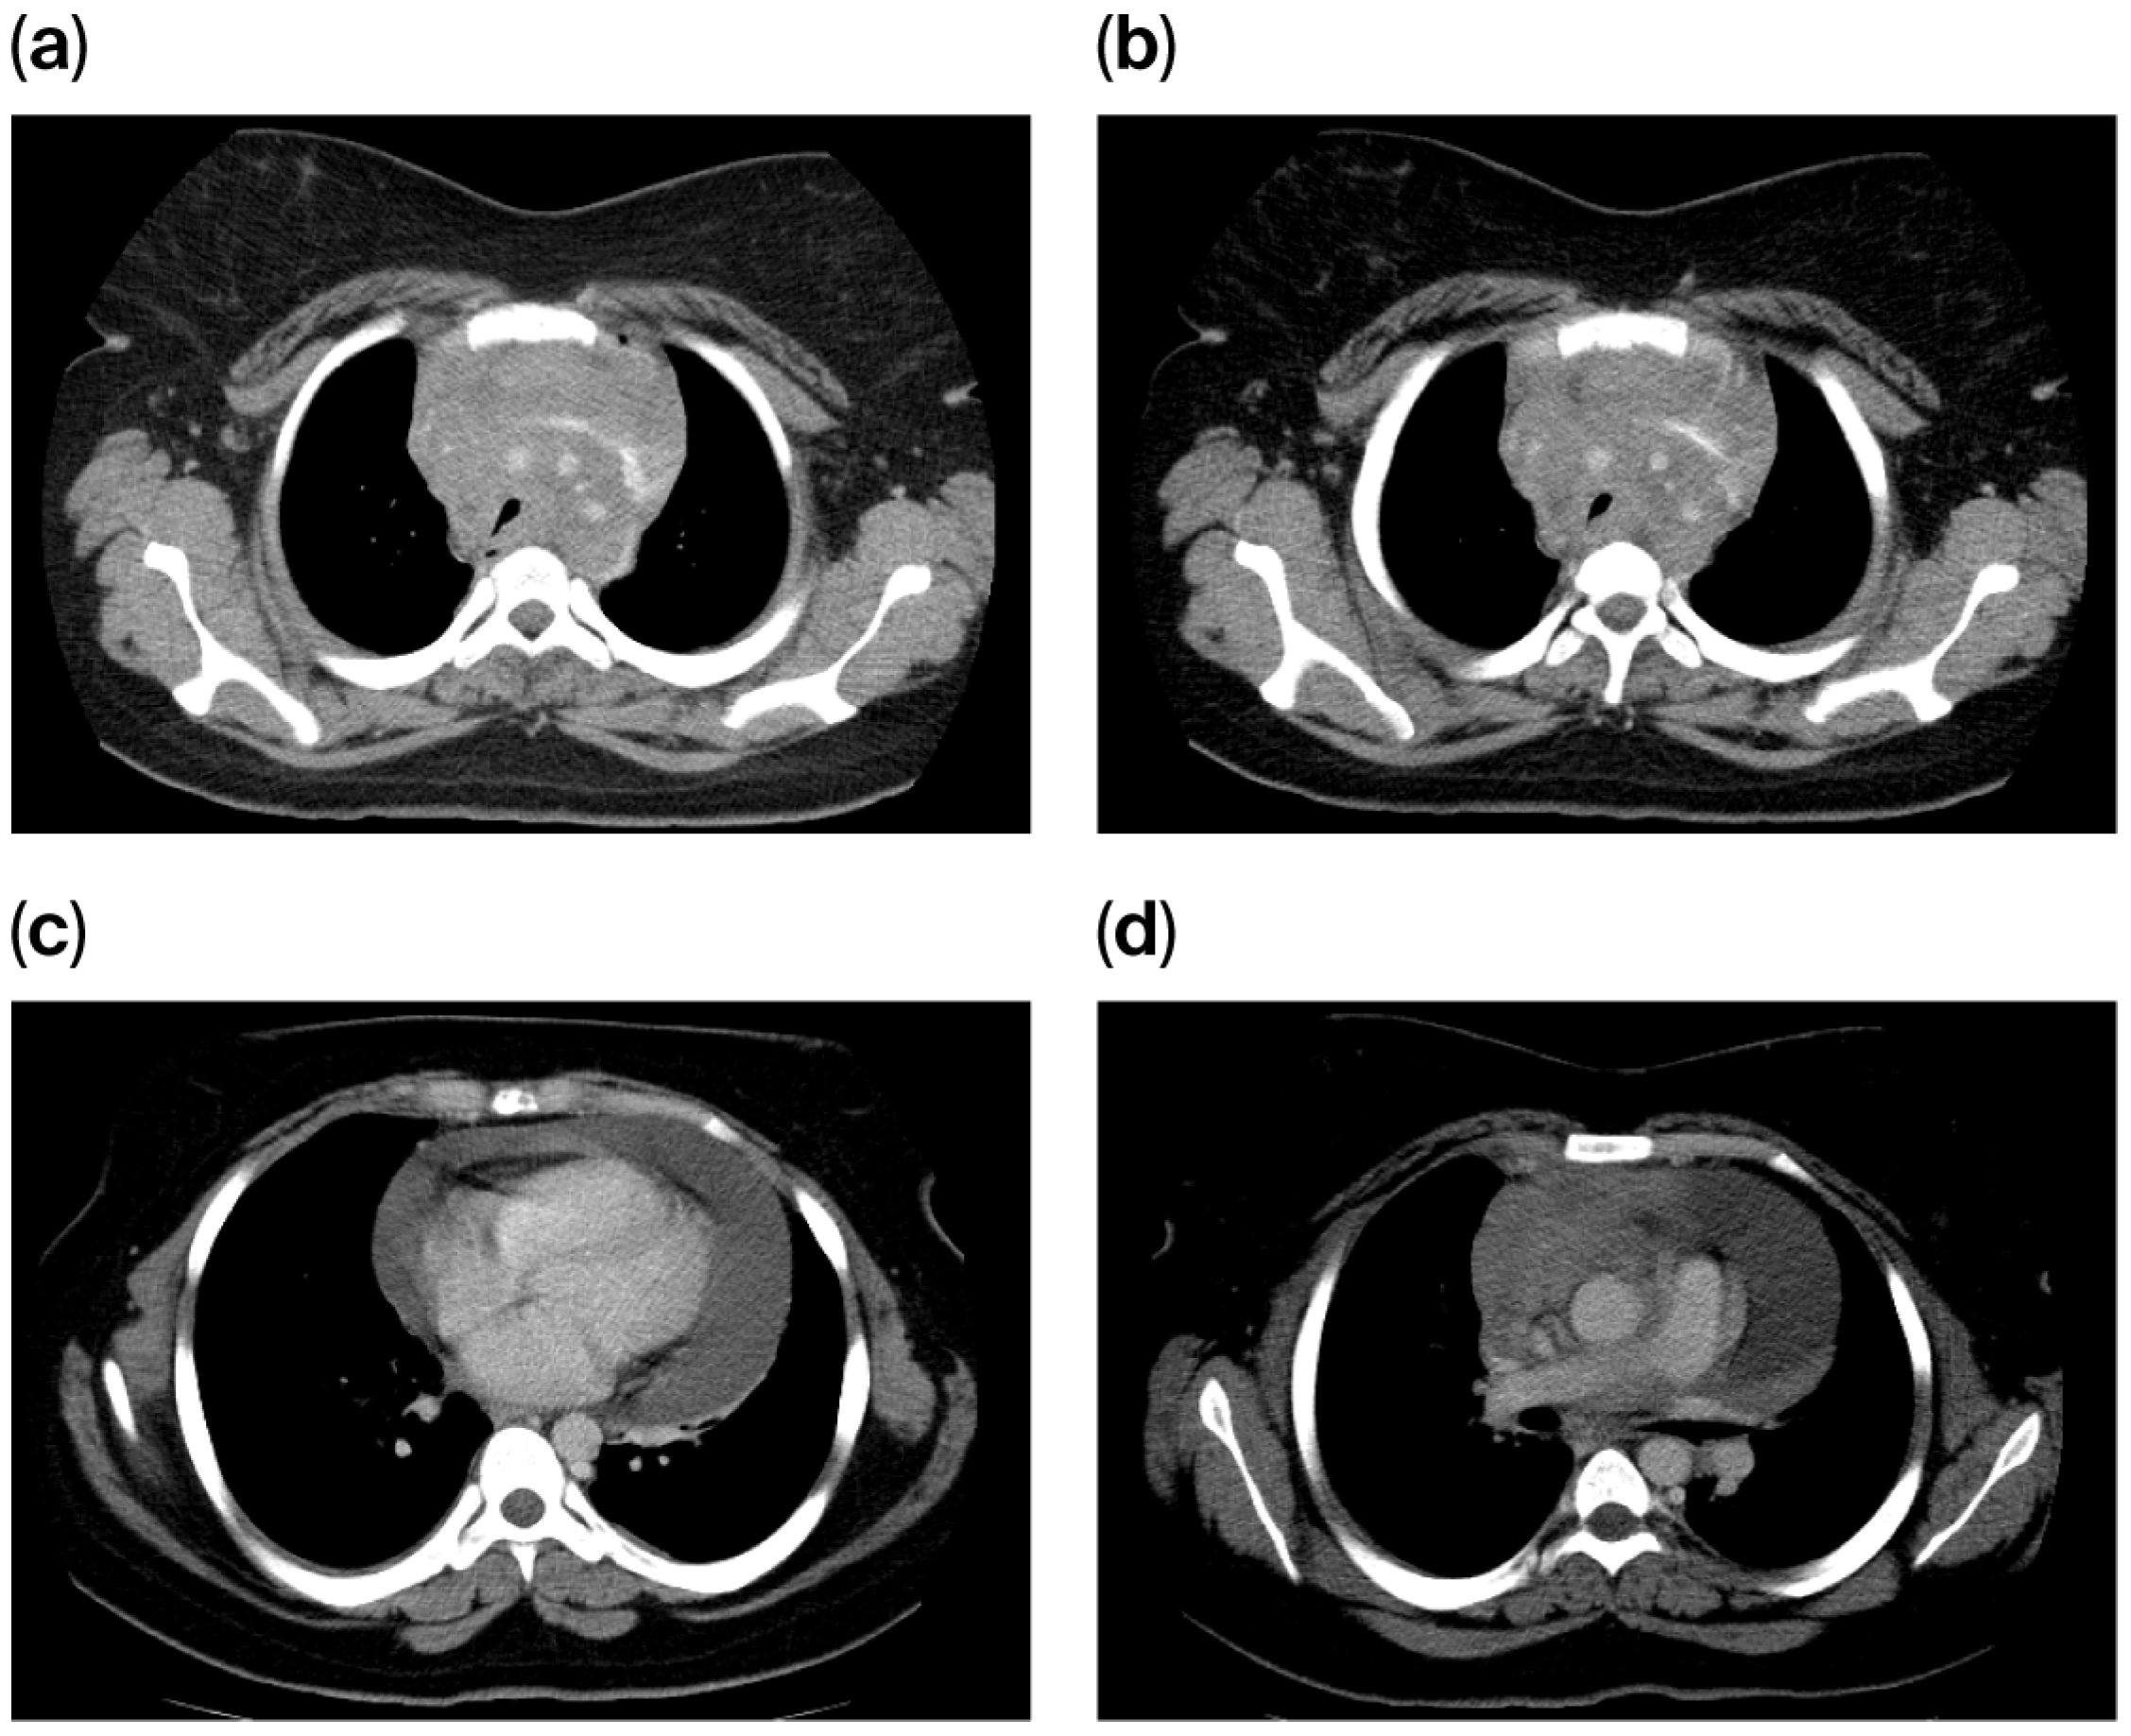

The chest computed tomography (CT) scan performed on 15 May 2013, demonstrated extensive mediastinal lymphadenopathy involving all nodal stations, resulting in the encasement and compression of the mediastinal vascular structures. A moderate-to-large circumferential pericardial effusion was noted, with a maximum thickness of 3.7 cm; however, no pleural effusions were identified. The pulmonary parenchyma was clear, with no evidence of focal or consolidative lesions. Visualized subdiaphragmatic structures, including the liver, spleen, and pancreas, appeared unremarkable, and no abdominal lymphadenopathy was detected (Figure 1).

Figure 1. (ad) CT scan at initial diagnosis (May 2013), demonstrating a mediastinal mass and a significant pericardial effusion measuring 3.7 cm in maximum depth.